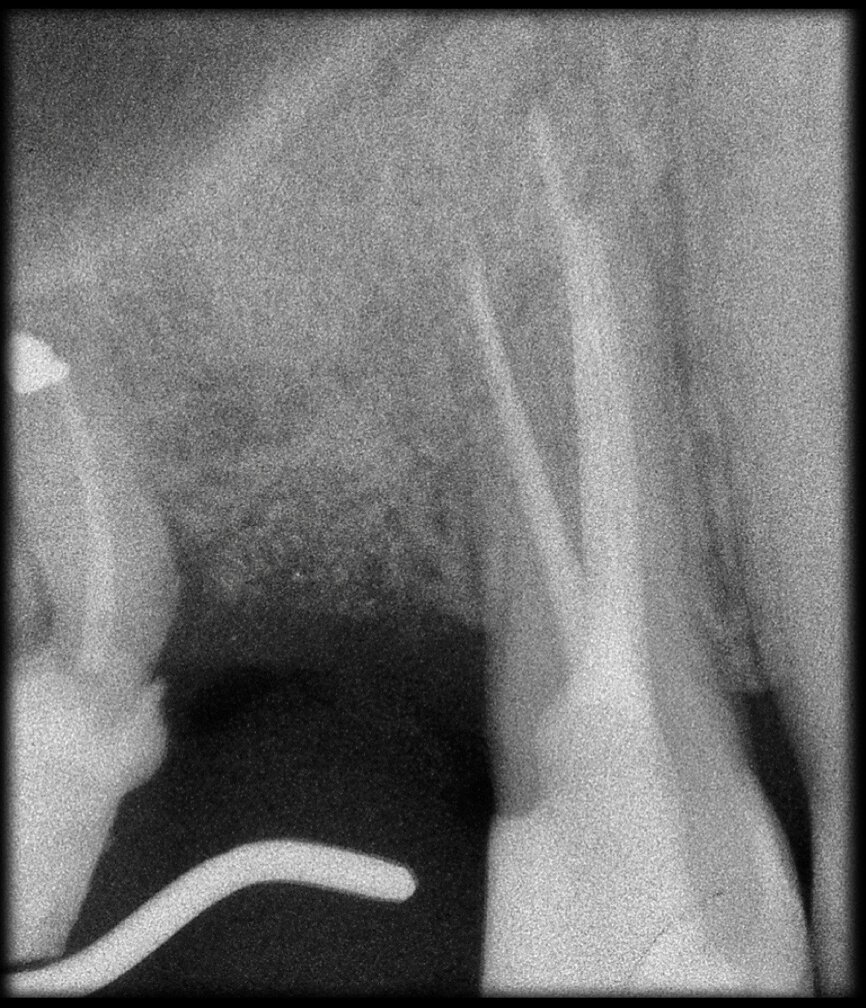

Preoperative CBCT evaluation is useful in cases requiring a surgical approach, not only in order to confirm the presence of a lesion but also to plan the procedure and, in particular, identify the type of surgical incision to be used, based on its size and location (Figs. 23–25). This specific case is characteristic of this situation. The intraoral radiograph did not make it possible to ascertain the extent of the lesion, which involved not only the apical region of the premolar but also a distal edentulous segment. This region would need to be treated with regenerative therapy in order to guarantee correct healing of the area, with subsequent insertion of a membrane, the flap must be protected using a totally different approach to that required for endodontic surgery. The intraoperative images illustrate the various stages of the procedure (Figs. 26–28). The CBCT scan performed 12 months later confirmed complete healing of the apical lesion and perfect graft integration (Figs. 29–31).